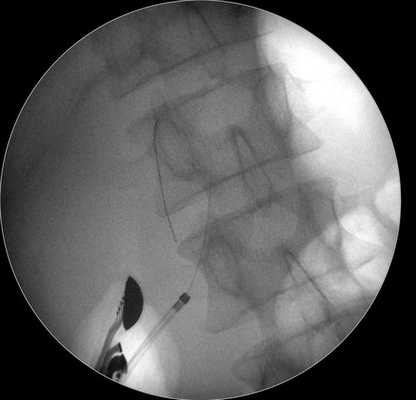

Затем под контролем рентгеноскопии в полость кисты вводится струна-проводник для установки пластикового стента (double pigtail) диаметром 10 Fr и длиной 10 см. Осуществляется рентгенологический и ультразвуковой контроль: он подтвердил, что дистальный конец стента располагается в просвете кисты, проксимальный - в луковице двенадцатиперстной кишки (рис. 5 в, рис. 6). При эндоскопическом осмотре оценивается область сформированного соустья для исключения кровотечения (рис. 7).

Рис. 5 (в)

Рис. 6